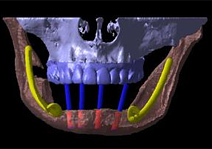

それでは実際にCTで撮影し、CTデータ3D立体構築画像変換検査したものがどう見えるのがご覧下さい。3次元でどこにどのようにインプラントを埋め込んでいけばいいのか、立体的に把握することができます。

吉本歯科医院でインプラント治療を行う患者さまの顎の状態は、CT画像だけでなくここまで立体化されたものが手術前には手元にあり、シミュレーションを行ってから実際の手術に入るような流れをとっております。

この中で、インプラントにおいて執刀する歯科医師が最も留意しなくてはならないのが下歯槽管神経との距離なのです。

インプラント体で下顎骨の中を走る神経やオトガイ孔から出た神経を傷つける可能性があるため手術の前には必ずCT撮影をし、適正な長さのインプラント体の選択が必要となります。

吉本歯科医院では、インプラント治療の前に必ず、血液検査、心電図検査、CT検査そしてCTデータ3D立体構築画像変換検査を受けて頂きます。

CT撮影だけでは不十分な部分をこの3D立体構築で把握します。

それはレントゲン写真だけでは絶対にわからない、3次元の患者さまのお口の様子が見えるからです。